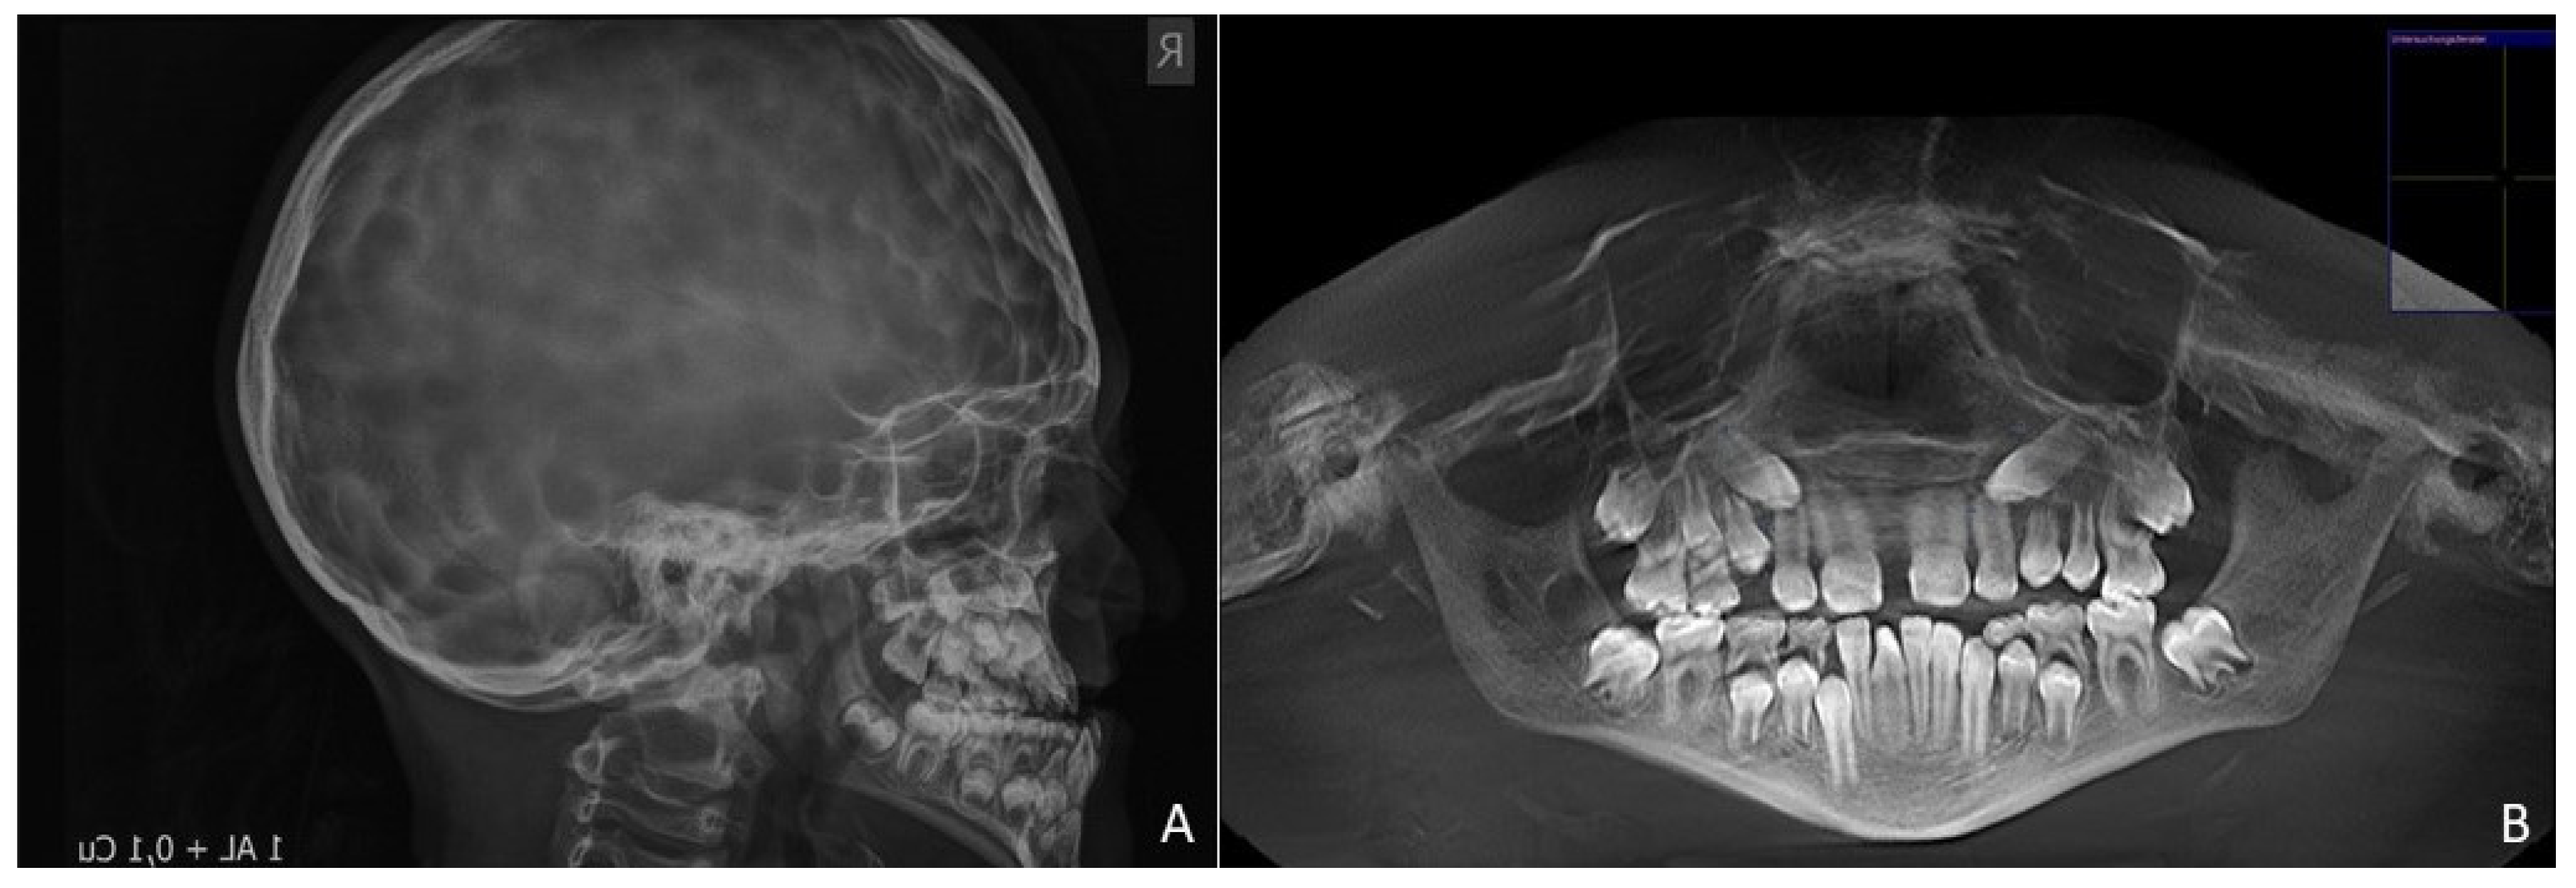

Distraction started seven days postoperatively by using a RED distractor and activating it twice daily for 14 days. A distraction rate of one millimeter per day was thus ensured [20]. In the subsequent ten-week retention phase, the traction wires remained fixed in the rigid external device, and retention by means of a face mask was therefore unnecessary. The multibracket appliance was in situ for a total of two years, followed by an orthodontic retention period of 28 months. At the end of the orthodontic therapy, the patient showed a well-balanced facial profile. Upper and lower dental arches were harmonized and stabilized in Class I occlusion (Figure 5). The slight but stable overjet fitted the minor skeletal Class III pattern, which was not fully corrected (WITS −5.3 mm, Figure 6). The patient was very adherent and attended a total of 33 orthodontic appointments during active treatment.

Figure 6. Posttreatment radiographs at the age of 15. (A). Lateral cephalogram at the end of the orthodontic retention period showing a slight relapse of the skeletal relationship. (B). Orthopantomogram showing the stable result with aligned canines.